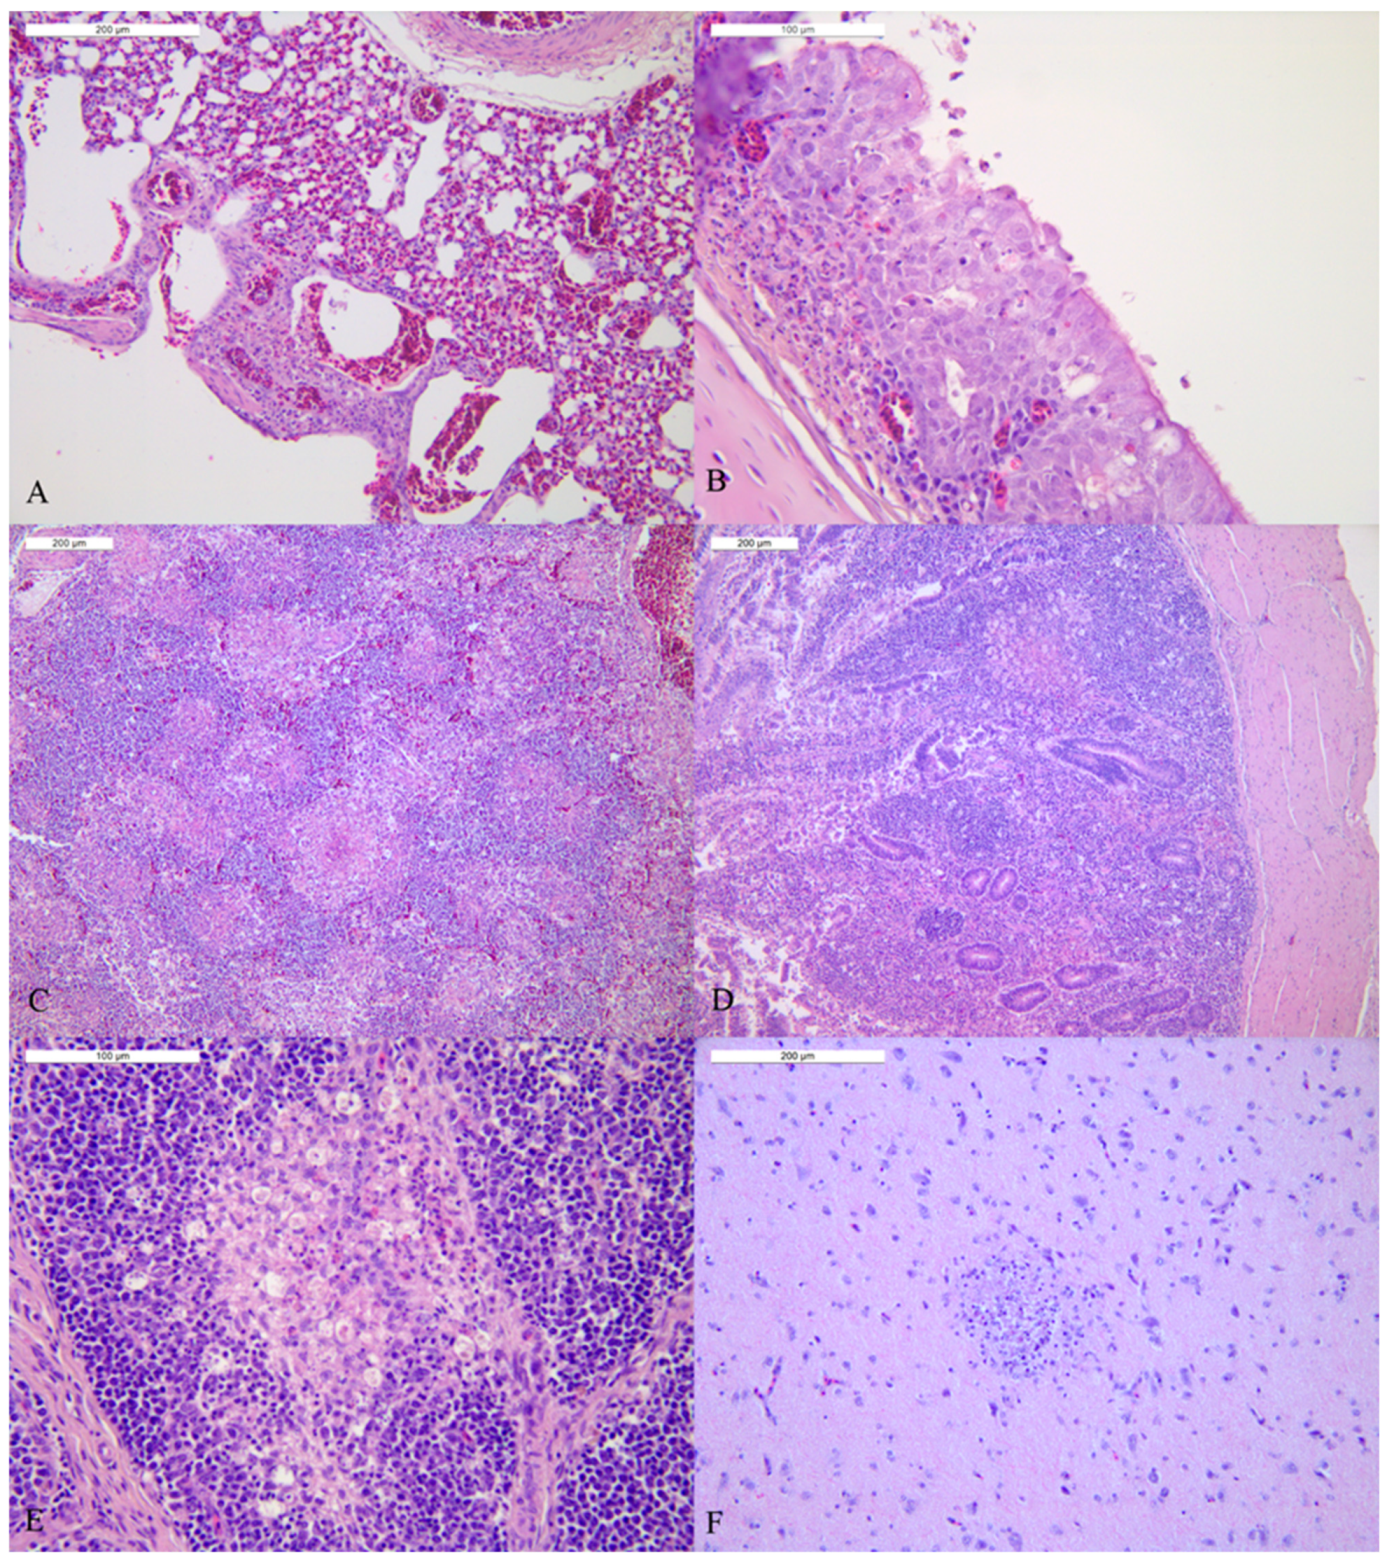

3.4. Study of Tissue Tropism and Pathogenesis (Pathobiology of HPAI Infection)

| Lung | 17.6 | +++ | 34.01 | − | 21.06 | +++ | 18.77 | +++ | 18.43 | +++ | Pneumocytes, endothelium |

| Trachea | 18.9 | + | 27.89 | − | 21.67 | ++ | 21.96 | ++ | 19.77 | +++ | Epithelial cells, macrophages, endothelium |

| Spleen | 19.07 | + | 36.13 | − | 19.81 | +++ | 22.08 | ++ | 23.32 | ++ | Macrophages, endothelium |

| Duodenum | 18.35 | ++ | 31.32 | − | 22.39 | + | 21.36 | + | 20.09 | +++ | Cellular debris in the crypts, epithelium, endothelium and plexi |

| Pancreas | 17.17 | +++ | 33.57 | − | 22.19 | ++ | 22.21 | + | 18.73 | +++ | Acinar necrotic epithelium |

| Cecal tonsil | 16.81 | +++ | 25.32 | + | neg | n.d. | 22.46 | ++ | 18.29 | ++ | Cellular Debris in the crypts, epithelium, necrotic area, endothelium |

| Bursa of Fabricius | 18.19 | +++ | 32.91 | − | 20.25 | + | 21.71 | ++ | 15.15 | ++ | Macrophages |

| Brain | 13.85 | +++ | 34.6 | − | 19.83 | ++ | 17.2 | +++ | 18.94 | +++ | Neurons, glial cells, ependymal |